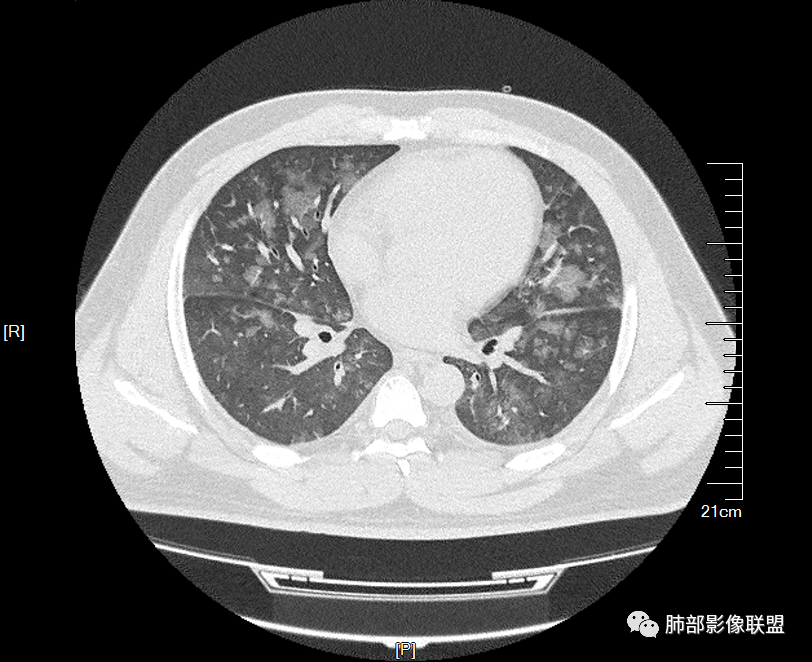

双肺多发弥漫性磨玻璃结节影,大小不一,形态不规则,部分融合,支气管未见明显扩张,部分血管束略增粗,叶裂胸膜增厚,临床有痛风,左足痛6天,考虑:1:痛风结节(一般实性结节,很少磨玻璃结节影)2:血管炎?3:病毒性肺炎(水痘-疱疹肺炎?)

双肺多发腺泡结节及磨玻璃,小叶间隔增厚(大网格状),腺泡结节内及磨玻璃内可见细网格影(小叶内间隔增厚),影像表现符合肺泡出血改变,血肌酐升高,考虑肺肾综合征。鉴别肺水肿。

年轻男性,痛风史,高血压史,肌酐高,左足痛6天入院。胸CT:双肺多发弥漫性磨玻璃结节影,大小不一,部分融合,上中下肺都有,中内带多,胸膜下少。部分血管束略增粗,小叶内间隔、小叶间隔增厚,下肺明显,左室大。叶裂胸膜增厚。临床有痛风,左足痛6天,考虑:心衰、间质性肺水肿?弥漫性肺泡出血?鉴别:MPA,肺肾综合征,痛风结节等。

双肺多发腺泡结节及斑片状磨玻璃影,边缘不清,后者内见细网格状改变,小叶间隔增厚,呼吸系统症状不明显,考虑肺水肿,过敏性肺泡炎代排

多发GGO结节,边界清,以全小叶、小叶中心为主:

小叶间隔增厚,无明显重力趋势

中轴间质稍增厚

中轴间质增厚,小叶间隔增厚,小叶内间质增厚,部分重力作用,双侧对称,胸水,按理淋巴道回流受阻有

1.间质性肺水肿 :小叶间隔增厚,尚光滑,支气管血管束增粗,胸膜或叶间裂增厚,肺内有磨玻璃密度影,有重力分布趋势。

2.肺泡性肺水肿 :

(1)中央型分布:以肺门为中心,两肺中内带对称分布的大片状实变,称为“蝶翼征”。常见于心源性及肾源性肺水肿患者。也可表现为磨玻璃密度病灶,弥漫性分布或以小叶中心性分布。

(2)弥漫型肺水肿:弥漫分布于两肺内的多发斑片状磨玻璃密度及实变影,大小和密度不等,可融合成大片状阴影,可见空气支气管征。